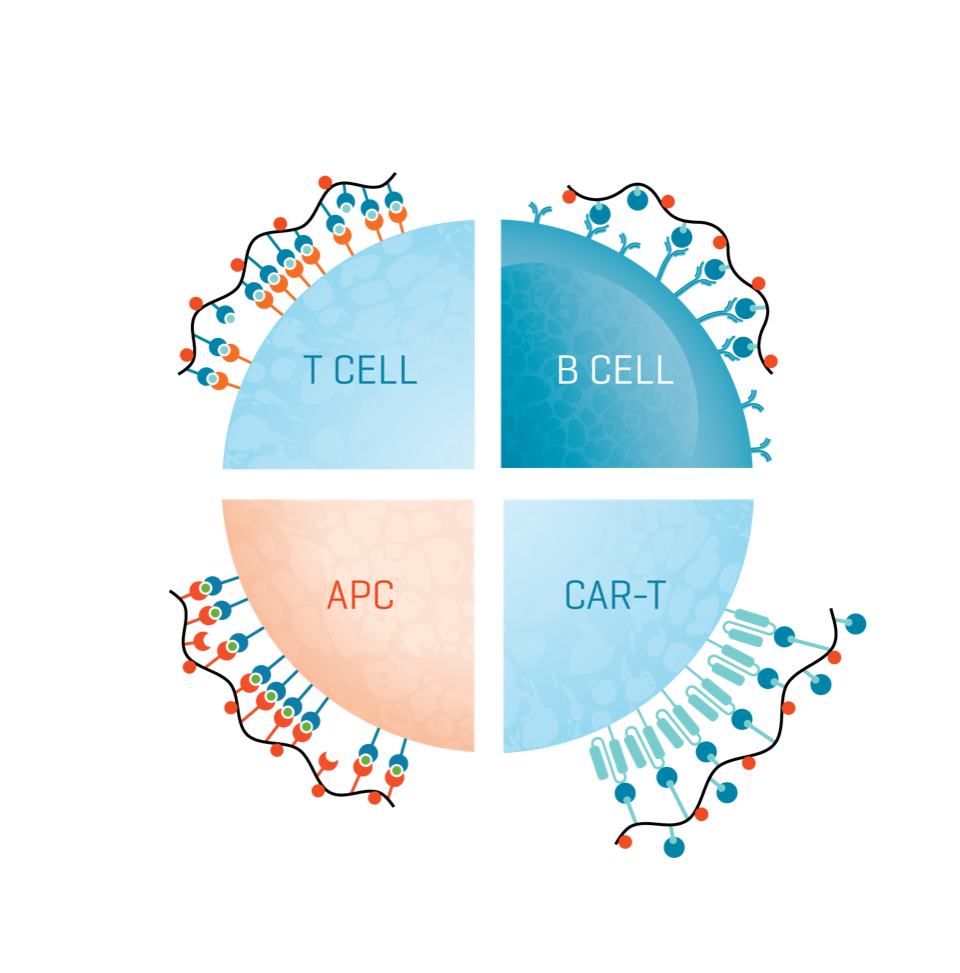

Reactions of the immune system to the presence of cancer cells are complex and varied. A diversity of immune cells interact in a collective response, each with different receptor affinities to specific tumor antigens.

T cells

T cells that have infiltrated a tumor (TILs) can be isolated, activated, expanded, and reinfused into the patient to mount a strong attack on the tumor. The same cells may also be equipped with a new receptor (TCR) to target specific cancer antigens.

CAR-T cells

T cells engineered with cancer-targeting chimeric antigen receptors (CARs), with the ability to target a specific protein. They are designed to recognize highly specific antigens and either kill tumor cells or modulate immune responses.

B cells

B cells produce antibodies and act as potent antigen-presenting cells to induce antitumor-specific T-cell responses. With well-defined epitopes and sensitive reagents, diverse B-cell populations can be stratified and their role in immunity revealed.